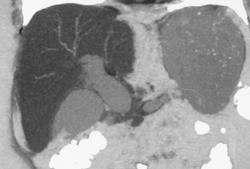

SMA Encased By Tumor